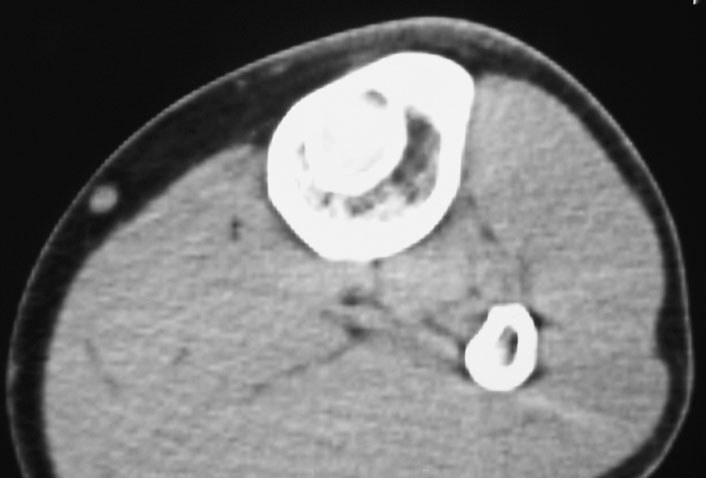

标题: CT19885:左胫骨上端肿瘤。 [打印本页]

标题: CT19885:左胫骨上端肿瘤。

男,20岁,医学院学生,11年前感左胫骨上端劳累后酸痛,曾由父母带到国内好几家有名望的医院诊治,但众说不一,所以基本上没有治疗。今年三月又开始出现症状,又到多家省级医院求治,但专家们的意见还是不能统一。各生化检查正常。mri考虑到胫骨上端良性血管瘤可能性大。ct考虑纤维瘤可能性大。请各位发表高见。

考虑胫骨多发性内生骨瘤。

胫骨多发性内生骨瘤可能。

考虑左胫骨良性骨肿瘤或骨肿瘤样病变(多发性内生骨瘤?骨纤维结构不良?)。

考虑胫骨多发性内生骨瘤可能。应该传骨窗。

考虑左胫骨良性骨肿瘤或骨肿瘤样病变(多发性内生骨瘤?骨纤维结构不良?)。骨梗死,纤维瘤。